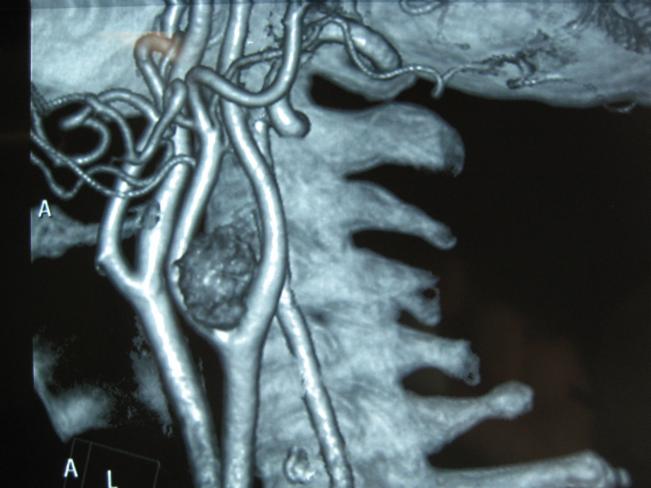

Su diagnóstico generalmente se realiza por la aparición de una masa lateral en el cuello

que a veces transmite el pulso de la arteria contigua. Mediante ECODOPPLER

podemos encontrar una masa que separa la bifurcación carotidea y llegar al diagnóstico definitivo mediante ANGIOTAC, ANGIORM O ARTERIOGRAFÍA.

Una vez diagnosticado, debe realizarse la resección quirúrgica precoz. Es un tumor que a medida que evoluciona, crece envolviendo las estructuras vasculares y nerviosas vecinas, lo cual aumenta la dificultad para la resección y las posibles complicaciones y secuelas neurológicas.